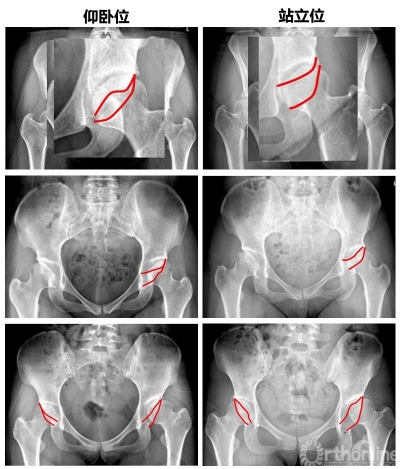

仰卧位和站立位的骨盆矢状面差异

图1. 骨盆的三维位置变化

随着人类祖先从四肢行走变成直立行走,骨盆也逐渐朝着适应站立位的方向进化。站立与行走是人体功能位,站立位也更能体现骨盆和髋臼周围肌肉和矢状面平衡和动态变化。但一般诊断时患者普遍以仰卧位姿势行X线片,这样获得的患者骨盆信息是否与站立时存在差异?

对了研究从仰卧位到站立位骨盆变化,张教授和团队对照了110例接受髋臼周围截骨(PAO)手术的发育性髋关节发育不良(DDH)患者[男性:32例(52hips),女性:78例(135hips)],与36名正常对照者在仰卧位和站立位的骨盆前后X线片。

图2 仰卧位与站立位髋臼前倾角变化

图3 DDH组与对照组骨盆角度对比

结果发现,骨盆从仰卧位到站立位,PSSC减小,骨盆后倾,髋臼前倾角增大,髋臼前覆盖减小。而对于DDH患者,为消除前侧不稳定,骨盆会发生代偿性前倾。因此DDH患者站立位时骨盆较正常人前倾增大。